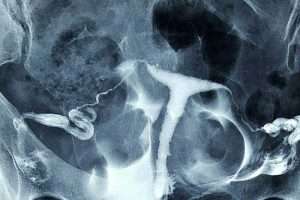

Sol Selektif Salpingografi